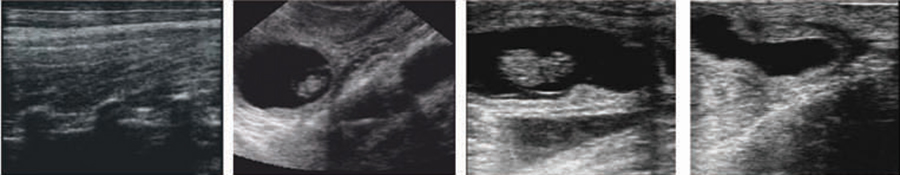

V7 手持式全数字超声诊断系统